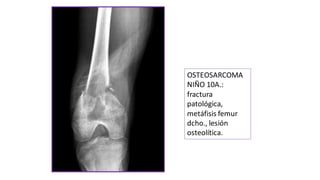

OSTEOSARCOMA

NIÑO 10A.:

fractura

patológica,

metáfisis femur

dcho., lesión

osteolítica.